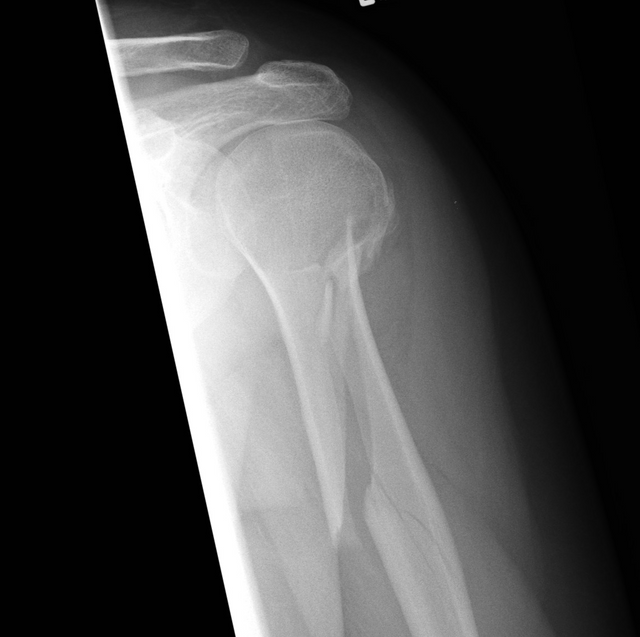

Q5

Bonus question (this may require some research) what sort of fracture is this?

Spiral fracture of the humerus